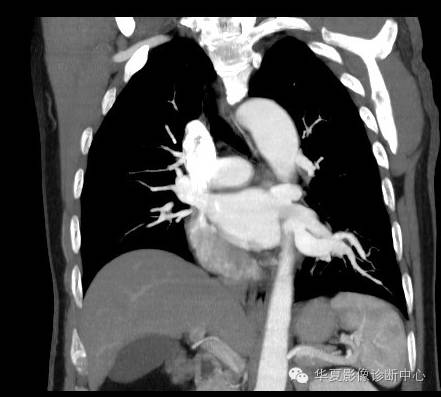

| 影像表现及分析: | 影像表现:定位左下叶;左下叶体积缩小,整体密度增高,支气管分布正常,其内见血管增多,但是走形正常,未见杂乱、迂曲的血管影;血管连向肺门下方软组织密度结节灶,结节与主动脉分界不清,增强后,见降主动脉发出异常粗大血管供血整个左下叶,左下肺动脉细小。 |

| 确诊依据: | CTA明确左下叶供血动脉为降主动脉发出 |

异常体动脉供应正常下肺基底段完整含义为起源于降主动脉的异常动脉供应下肺基底段,而基底段支气管树和肺实质正常,同时基底段肺动脉缺如或狭窄【大部分缺如(完全型),部分狭窄(不完全型)】;95%以上累及左下肺,因此也称为异常体动脉供应正常左下肺基底段。 病因尚未明确,可能是胚胎发育时期供应肺芽的背主动脉原始小分支退化不全,与肺实质形成异常连接,并影响肺动脉与肺血管床连接而导致此部位肺动脉发育不良,而支气管、肺组织的发育未受影响。本病的病理生理基础为左向左的分流,体动脉供应的肺组织充血,体循环的高压可增加肺血管床的压力和左心负荷,同时也增加肺循环量和压力而增加右心负荷,导致各种临床症群。本病可无临床症状,部分患者可有咯血、呼吸道感染、呼吸困难、充血性心力衰竭。 影像表现:左肺下叶体积缩小,整体密度稍增高,支气管树走形、分布正常,血管增多、稍增粗;增强后显示左下肺动脉幼小,甚至不发育;下叶由主动脉发出的粗大血管供血。 |